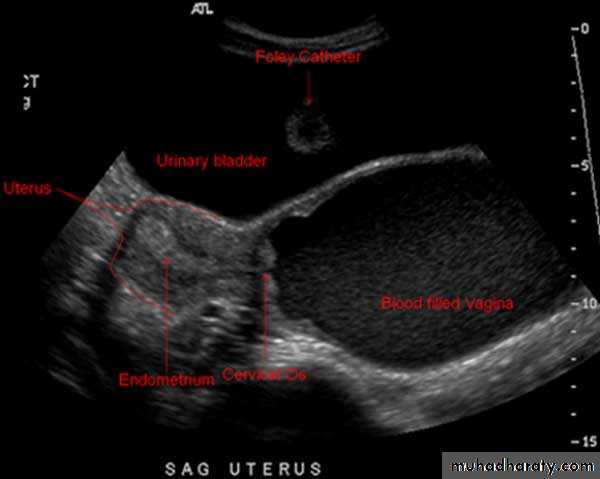

Normal Uterus

Normal Uterus in longitudinal view